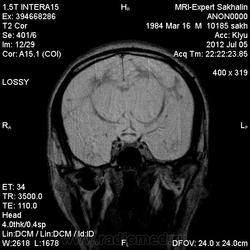

1 случай -локальная гемиатрофия.2 случай-диффузная.

Молодой человек после автомобильной аварии.3 года лежит.Двигаются только глаза.Зрелище душещипательное.

Евгений, конечно же, мои случаи не являются "чистой" атрофией-согласна.Мне пока не встречались случаи болезни Пика, Альцгеймера и другие "чистой воды" атрофии.Второй случай- состояние после длительной комы вследствие автодорожной травмы 3 года назад.Пациент проходил исследование в прошлом году , в этом родители привезли на динамику.